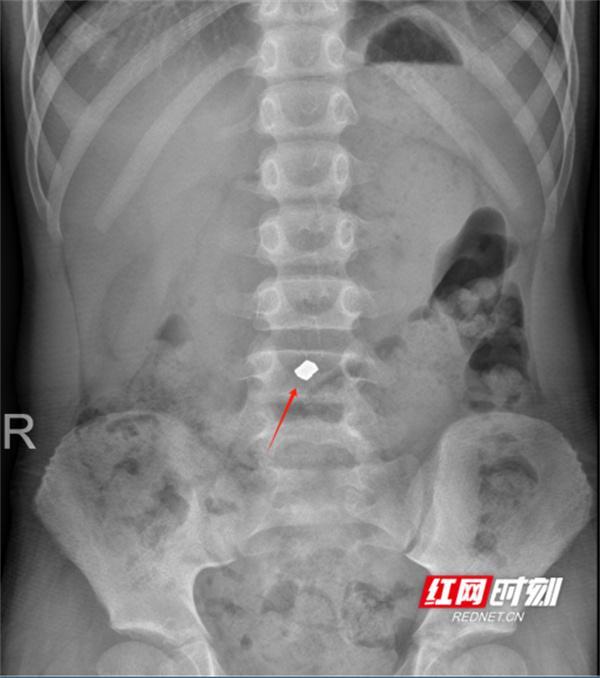

红色箭头处为食道异物(鱼刺)。

X线平片检查:适用于金属或高密度异物,胸、腹部正侧位X线片可了解异物数量、大小、形态及位置,硬币类圆钝消化道异物需随访X线,以观察异物的位置,是否存在嵌顿的情况。